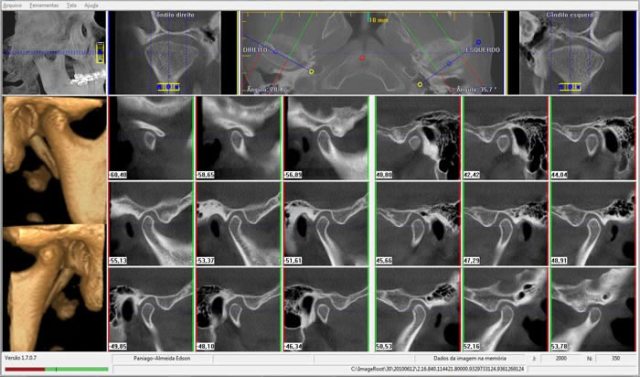

CASO 1 - Anquilose de ATM

Paciente com assimetria, limitação de abertura bucal. Observa-se união óssea da porção posterior e lateral do côndilo ao esfeóide e zigomático.